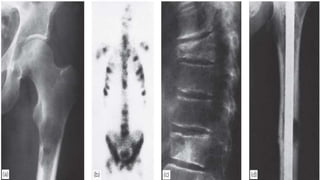

After 50 years, bone metastases are seen more frequently

than all primary malignant bone tumours together.

The commonest source is carcinoma of the breast; next in

frequency are carcinomas of the prostate, kidney, lung,

thyroid, bladder and gastrointestinal tract.

In about 10% of cases no primary tumour is found.

The commonest sites for bone metastases are the

vertebrae, pelvis, the proximal half of the femur and the

humerus.

Metastases are usually osteolytic, and pathological

fractures are common while osteoblastic lesions are

uncommon; they usually occur in prostatic carcinoma.

Pain is the commonest – and often the only – clinical feature.

Some deposits remain clinically silent and are discovered

incidentally on x-ray, or after a pathological fracture.

Symptoms of hypercalcaemia may occur (and are often

missed) in patients with skeletal metastases. These include

anorexia, nausea, thirst, polyuria, abdominal pain, general

weakness and depression.

The ESR may be increased and the haemoglobin

concentration is usually low. The serum alkaline phosphatase

concentration is often increased, and in prostatic carcinoma

the acid phosphatase also is elevated.

 On x-ray examination skeletal deposits usually appear as

rarefied areas in the medulla or patches of bone destruction

in the cortex. Vertebral collapse is also common.

METASTATIC BONE DISEASE After50 years, bone metastases are seen more frequently than all primary malignant bone tumours together. The commonest source is carcinoma of the breast; next in frequency are carcinomas of the prostate, kidney, lung, thyroid, bladder and gastrointestinal tract. In about 10% of cases no primary tumour is found. The commonest sites for bone metastases are the vertebrae, pelvis, the proximal half of the femur and the humerus. Metastases are usually osteolytic, and pathological fractures are common while osteoblastic lesions are uncommon; they usually occur in prostatic carcinoma.

Pain is thecommonest – and often the only – clinical feature. Some deposits remain clinically silent and are discovered incidentally on x-ray, or after a pathological fracture. Symptoms of hypercalcaemia may occur (and are often missed) in patients with skeletal metastases. These include anorexia, nausea, thirst, polyuria, abdominal pain, general weakness and depression. The ESR may be increased and the haemoglobin concentration is usually low. The serum alkaline phosphatase concentration is often increased, and in prostatic carcinoma the acid phosphatase also is elevated.  On x-ray examination skeletal deposits usually appear as rarefied areas in the medulla or patches of bone destruction in the cortex. Vertebral collapse is also common.